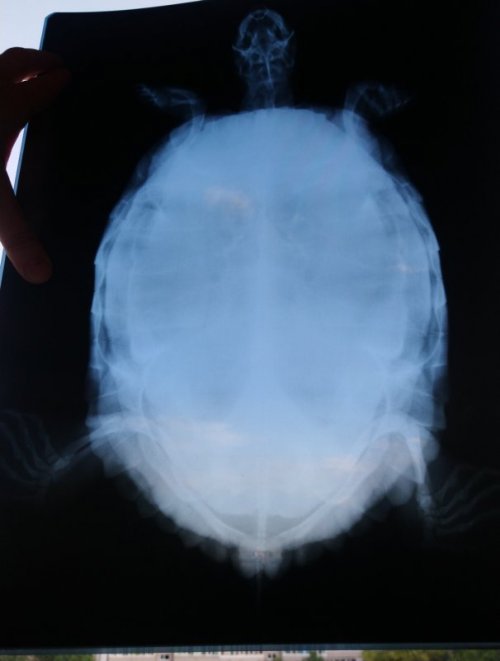

NataLiRED Ваше имя: Наталья Локация: Арзамас, РФ Опубликовано: 13 июля 2021 Автор Опубликовано: 13 июля 2021 Вернулись с рентгена. Яиц вроде не видно. Сделали ей там три снимка. Первый - обзорный с расстояния 90 см, 50 кВ на 10 мА\с. Два других - с расстояния меньше (не уверена в см), 50 и 55 кВ / 15 мА\с. Взвесились там. И все так и есть. Вес 3,05 кг. Возможно давнее взвешивание в мешке было так себе в плане точности. Борглюконат кальция и Элеовит куплены.

Консультанты moth Ваше имя: Мария Локация: Москва Опубликовано: 14 июля 2021 Консультанты Опубликовано: 14 июля 2021 @NataLiRED в соседней теме была похожая ситуация, там у черепахи в итоге оказалась пневмония, именно поэтому я советую брать хотя бы онлайн консультацию, но именно у врача-герпетолога. Т.к. мы тут не врачи и даём рекомендации на основе статистики и симптомов, а в реальности всё может быть не так. Тем более, что яиц у неё нет. Я могу расписать Вам схему кальция и Элеовита, но тут может быть дело в другом. 300р не такая большая сумма, подумайте о консультации. Врач консультирует в своём телеграмм канале, Вам нужно написать свой ник и я Вас добавлю, там уже будете общаться непосредственно с герпетологом. Для диагностики потребуются снимки в других проекциях, чтобы посмотреть лёгкие, но это уже врач Вам всё расскажет. Если не хотите брать платную консультацию - скажите, я распишу тогда схему кальция.